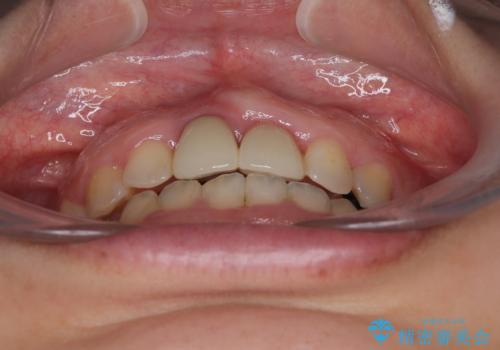

- 前歯のデコボコと、着色が著しい保険診療の前歯クラウンを気にして来院された患者様です。

左上の犬歯が埋伏しており、CT画像より萌出は困難と判断されたため、残存している歯にて歯列と咬合を整えることとしました。

前歯のクラウンは変色が顕著なため、矯正治療後にオールセラミッククラウンによる補綴治療を行うこととしました。